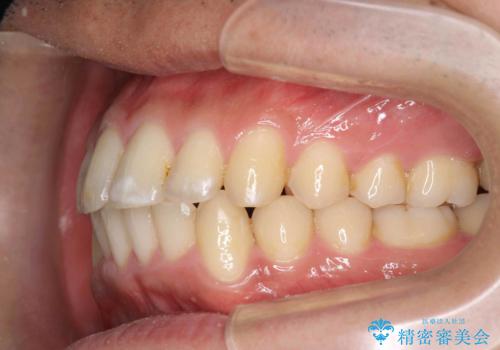

歯を抜かない矯正 奥歯のすれ違い咬合 下の八重歯

- 前歯のガタガタを主訴に来院。

奥歯はすれ違ってしまっていました。

口元も出ておらず、非抜歯を希望されたため、IPR(歯を削る処置)でスペースを確保しました。

上顎両側7番(一番奥の歯)はすれ違っており、虫歯になっていました。